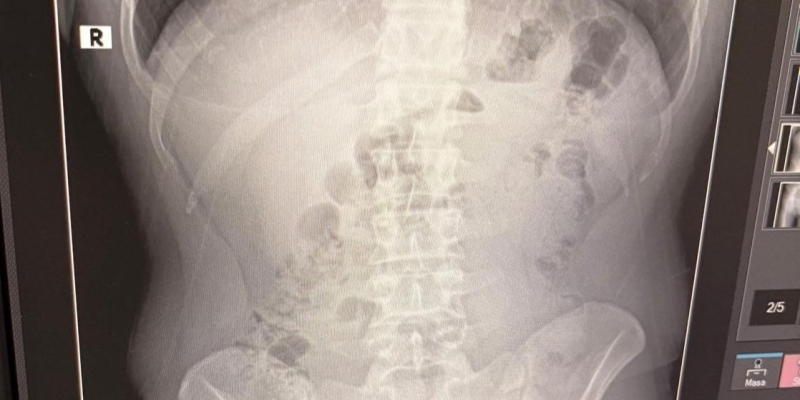

Adreste yapılan arama sırasında ekipler, şüphelilerden birinin üstünde 1 adet kapsül ele geçirdi. Şüphe üzerine tüm şüpheliler hastaneye götürüldü ve yapılan röntgen kontrollerinde 3 kişinin midelerinde kapsül içine gizlenmiş metamfetamin tespit edildi.

Hastanede tedavi altına alınan şüphelilerin vücudundan kapsüller çıkarılırken, adreste ele geçirilenlerle birlikte toplam 1 kilo 516 gram metamfetamin ele geçirildi.